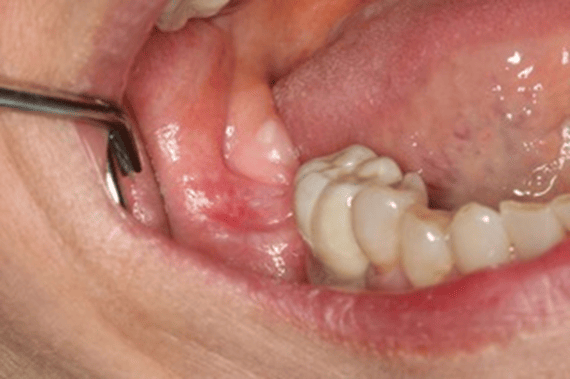

Figure 1 is a photo of a 4×6 mm red and white, flat lesion found on the right posterior mandibular alveolar tissue.

The patient complained of an intermittent “burning” sensation but was otherwise asymptomatic.

Due to the clinical presentation and potential for malignancy, the surgeon chose to perform an incisional biopsy of the area. The pathology report revealed “lichenoid mucositis with epithelial atypia” as the diagnosis.

The patient is not taking either NSAIDs or ACE medications, so this can be ruled out as a cause for the OLL.

As the picture shows, a nearby ceramic crown could be causing the OLL. But this cannot be determined unless the crown is removed and the area is allowed time to heal.

The patient has been informed of the potential for malignancy and is being monitored closely by the surgeon who performed the biopsy. If the surgeon notices any changes to the lesion, a future biopsy may be warranted.